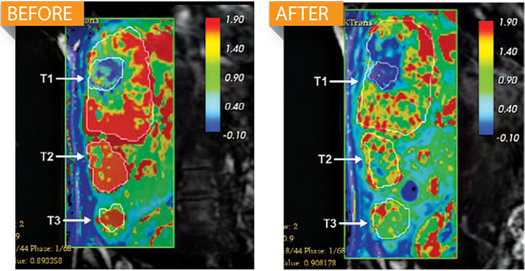

核磁共振掃描顯示,使用ALN-VSP療法后,肝臟腫瘤中的血流量(紅色)明顯減少。

到今年6月,阿爾尼拉姆公司稱,通過“喚醒”人體自身的一種很少使用的免疫防御系統(tǒng),ALN-VSP成功切斷肝癌患者體內(nèi)腫瘤62%的血流量。在治療肝癌時(shí),傳統(tǒng)藥物一般使用消除致病蛋白質(zhì)的方法,而ALN-VSP則通過核糖核酸干擾(RNAi)療法直接阻止細(xì)胞生成致病蛋白質(zhì)。